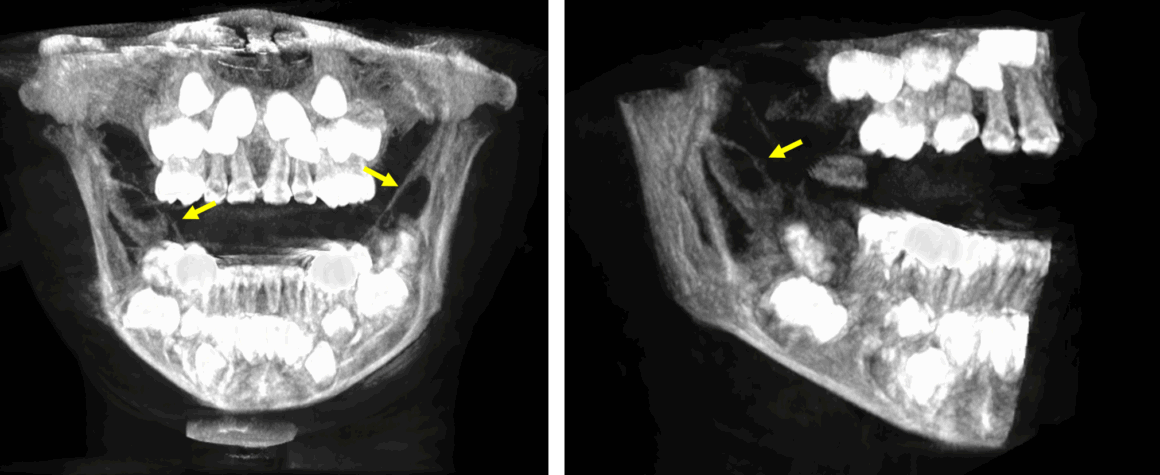

Fig.1

En la evaluación de una tomografía de ambos maxilares, se realizó la reconstrucción panorámica (Fig.1) donde se observa en el lado derecho de la mandíbula una lesión osteolítica que condiciona la expansión del borde anterior de la rama ascendente comprometiendo los tercios inferior, medio y superior. De forma contralateral, se observa también una lesion osteolítica de menor tamaño en comparación que la lesión del lado derecho, la cual se observa comprometiendo el tercio medio de la rama ascendente condicionando la expansión de la cortical ósea de su borde anterior (flechas rojas).

Fig.2

En cortes coronales (Fig.2) se observan ambas lesiones osteolítica se observa el compromiso de las tablas óseas en ambas ramas ascendente. Nótese que la lesión del lado derecho supera en volumen a la lesion contralateral.